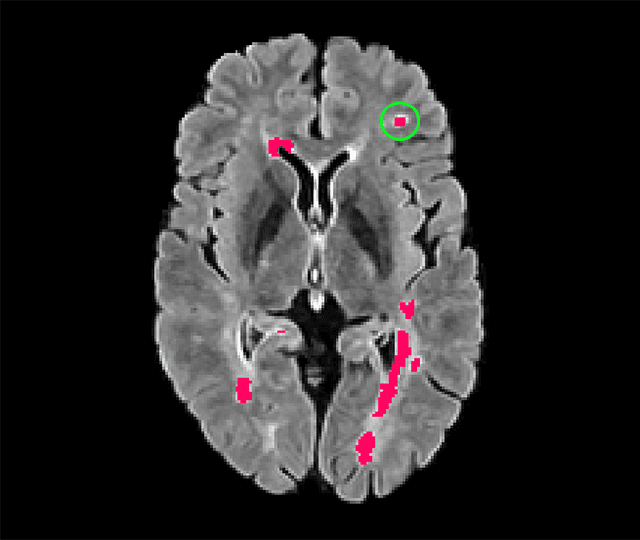

Abstract:Deep convolutional neural networks have proven to be remarkably effective in semantic segmentation tasks. Most popular loss functions were introduced targeting improved volumetric scores, such as the Sorensen Dice coefficient. By design, DSC can tackle class imbalance; however, it does not recognize instance imbalance within a class. As a result, a large foreground instance can dominate minor instances and still produce a satisfactory Sorensen Dice coefficient. Nevertheless, missing out on instances will lead to poor detection performance. This represents a critical issue in applications such as disease progression monitoring. For example, it is imperative to locate and surveil small-scale lesions in the follow-up of multiple sclerosis patients. We propose a novel family of loss functions, nicknamed blob loss, primarily aimed at maximizing instance-level detection metrics, such as F1 score and sensitivity. Blob loss is designed for semantic segmentation problems in which the instances are the connected components within a class. We extensively evaluate a DSC-based blob loss in five complex 3D semantic segmentation tasks featuring pronounced instance heterogeneity in terms of texture and morphology. Compared to soft Dice loss, we achieve 5 percent improvement for MS lesions, 3 percent improvement for liver tumor, and an average 2 percent improvement for Microscopy segmentation tasks considering F1 score.